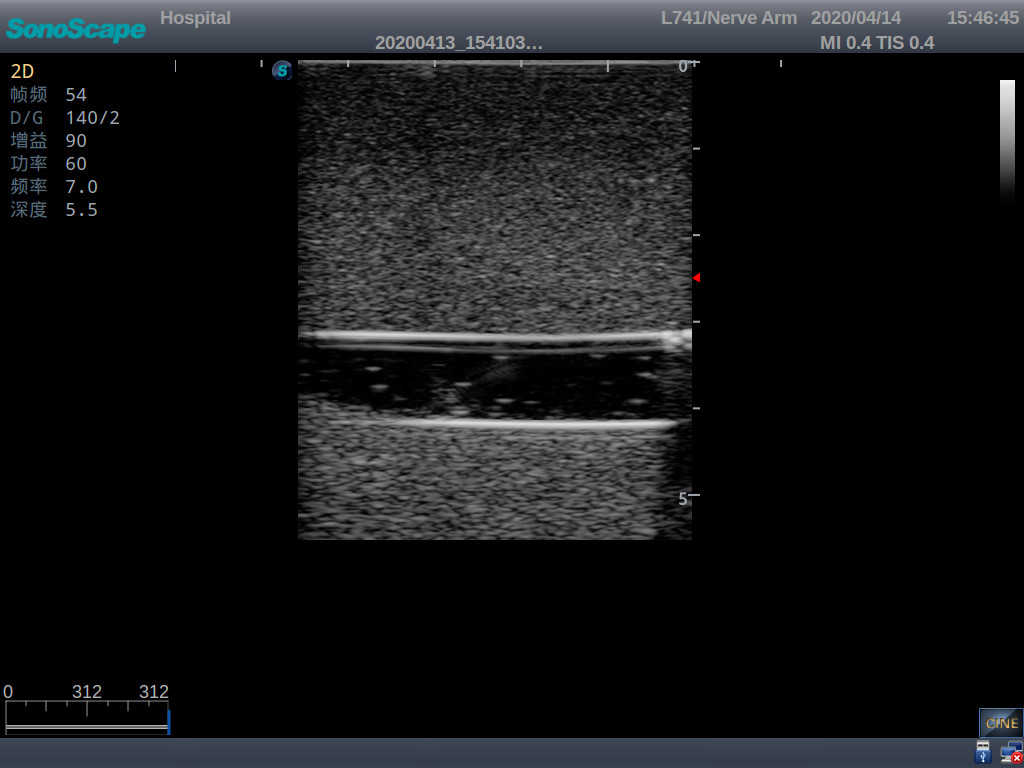

2)   It can be used by real ultrasound machines

3)   Clear and real images of the tissues and organs (basilic vein and superior vena cava)

4)   When conducting vascular puncture, the piercing can be truly felt, and venous blood outflow can be seen

5)   Observe the guide wire marches